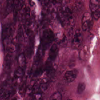

The definition of classes in our RC data is slightly different from the one coming with the CRC dataset. Therefore, we grouped corresponding classes as described in Table 2, which resulted in a 6-class problem, used to evaluate the performance of the trained ConvNet applied to CRC data. Applying the ConvNet directly to CRC data gave a poor accuracy value of 50.96% (experiment A). Based on this result, we investigated the role of staining in this classification task. For this purpose, we selected a representative RC image from the RC cohort as the template image to define the mapping parameters for the SN1 and SN2 algorithms999The function for SN1 is available in the form of look-up table at https://github.com/francescociompi/stain-normalization-isbi-2017. Successively, we stain-normalized patches in the CRC dataset and classified it again with the same ConvNet. Stain normalization allowed to remarkably improve the accuracy by more than 20%, reaching values of 75.55% (experiment B) and 73.99% accuracy for SN1 and SN2 respectively. Besides the difference in accuracy, we found that SN2 failed to normalize 3 patches of adipose tissue, and it tends to force color normalization regardless of the type of tissue considered. As an example, in Figure 4, two CRC patches are depicted, containing tumor and blood cells respectively. While both SN1 and SN2 correctly normalize stain for the tumor patch, the characteristic red color of blood cells is completely lost using SN2, while SN1 keeps a substantial component of the red channel.